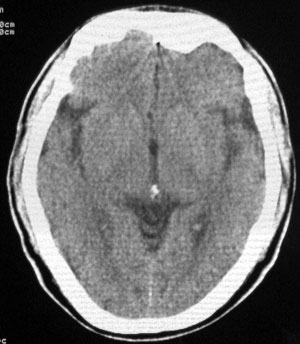

男性,65岁,头疼。 看看这大脑镰,ct值约83hu .

楼主的意思是让我们看大脑镰串珠样钙化,虽然ct值83hu ,也应该是钙化.(循环渐进).

男性,65岁,头疼。 看看这大脑镰,ct值约83hu .考虑蛛血,应该结合临床

感觉应该是生理性钙化

是生理性钙化

头痛与大脑镰钙化应该关系不大。

没有问题的!老年人!头痛的原因很多!大脑镰的钙化这样年龄的病人可以不提示!

大脑镰钙化,应该没有疑问吧